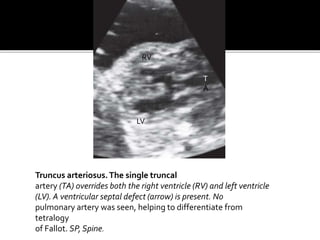

Truncus arteriosus.The single truncal

artery (TA) overrides both the right ventricle (RV) and left ventricle

(LV). A ventricular septal defect (arrow) is present. No

pulmonary artery was seen, helping to differentiate from

tetralogy

of Fallot. SP, Spine.

 1.3% offetal cardiac anomalies .  Characterised by a single large vessel arising from the base of the heart .almost all cases have VSD.The truncal valve may have 2-6 cusps and generally overrides the ventricular septum .  4 types by collett and edwards –  1) type 1 – has a pulmonary artery that bifurcates into rt and lt branches after it arises from the ascending portion of truncal vessel .

• 53.

 2) type2 – has rt and lt pul arteries arising separately from the posterior truncus .  3) type 3- pul arteries that arise from the sides of the proximal truncus .  4) type 4- has systemic collateral vessels from the descending aorta as the source of flow .  the single large truncal artery with overriding of the ventricular septum and an associatedVSD identified on 4 chamber and outflow tract views .

Truncus arteriosus.The singletruncal artery (TA) overrides both the right ventricle (RV) and left ventricle (LV). A ventricular septal defect (arrow) is present. No pulmonary artery was seen, helping to differentiate from tetralogy of Fallot. SP, Spine. T A RV LV